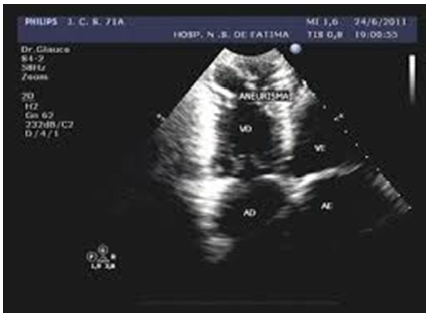

Paciente, queixando-se de cansaço aos esforços, apresenta BRD ao ECG. A imagem ecocardiográfica está apresentada a seguir. Qual é o diagnóstico mais provável?

Miocardiopatia chagásica.